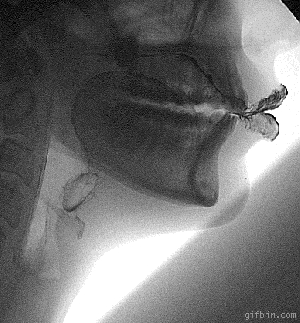

물 마실 때 X-Ray